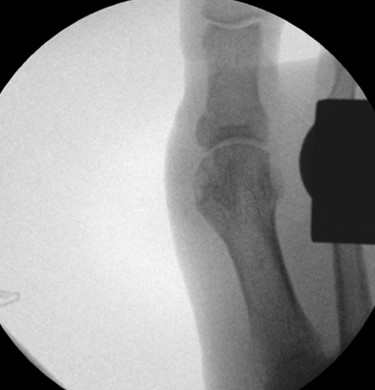

• Röntgenaufnahme des Fußes (unter Belastung) in dorsoplantarem und seitlichen Strahlengang (Abb. 3) und präoperative Fotodokumentation.

• Beurteilung des proximalen Gelenkflächenwinkels der Grundphalanx (Proximal Phalangeal Articular Angle, PPAA) des Hallux valgus interphalangeuswinkels (Hallux interphalangeus Angle, HIA) sowie des proximalen zum distalen Gelenksflächenwinkel (Proximal to Distal Phalangeal Articular Angle, PDPAA) 6789 (Abb. 2).

• Bildverstärker.

Operationstechnik (Text und Fotos)